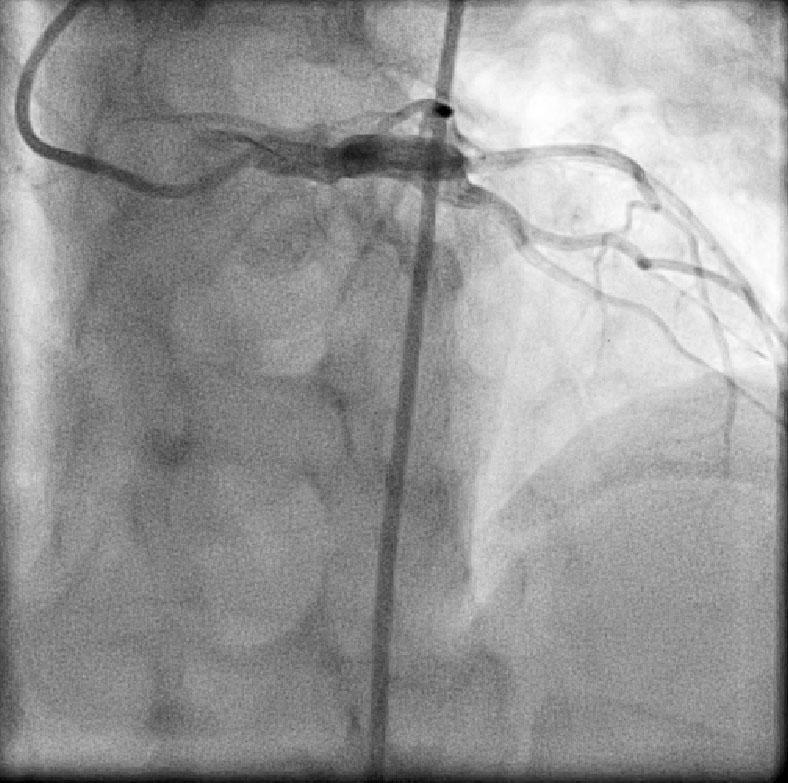

CABG in Kawasakis with Coronary Aneurysms

Angiogram prior to Primary PTCA